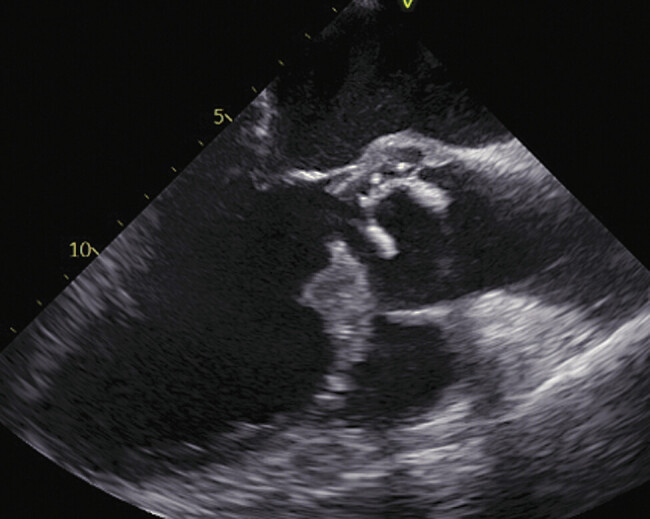

Case description: Emergency surgery was required for a 72-year-old male patient who was in cardiogenic shock due to severe aortic regurgitation resulting from acute prosthetic valve endocarditis. Due to atrial fibrillation, the patient was on apixaban, a factor Xa (FXa) inhibitor anticoagulant, until surgery. We used the ADVanced Organ Support (ADVOS) albumin hemodialysis system postoperatively to treat persisting shock with multi-organ failure, acidosis, and DOAC removal. Serial drug-level measurements revealed strongly accelerated apixaban clearance. In line with this, we observed only moderate drainage losses.

Abstract Image